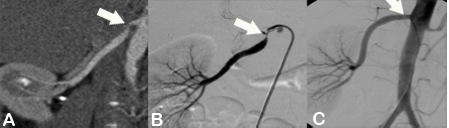

Die Abdomensonographie ist als Screeninguntersuchung und für eine routinemäßige Verlaufskontrolle bei Aneurysmen gut geeignet. Zur exakten Bestimmung der Größe und Morphologie wird jedoch eine Computertomographie (Abb. 1), in Ausnahmefällen eine Magnetresonanztomographie, durchgeführt.

Alternativ zur offenen chirurgischen Therapie eines Aortenaneurysmas besteht die Möglichkeit einer endovaskulären Aneurysmaausschaltung mittels eines Stentgrafts (gewebeummanteltes Metallgittergeflecht). Voraussetzung für die endovaskuläre Therapie ist jedoch eine anatomische Eignung, welche eine ausreichende Weite der Beckengefäße und nötige Verankerungszonen für den Stentgraft mit sich bringt. Die Stentgraft Implantation wird von Interventionellen Radiologen in Zusammenarbeit mit Anästhesist:innen und Gefäßchirurg:innen durchgeführt. Der Eingriff erfolgt unter Spinalanästhesie oder einer Allgemeinnarkose. Der Zugang zum Aneurysma wird üblicherweise durch einen kurzen Schnitt in der Leiste geschaffen. Zur Darstellung des Aneurysmas wird zuerst eine Angiographie der Bauchaorta durchgeführt (Abb.2). Folglich wird unter Röntgendurchleuchtung der Stentgraft über einen Führungsdraht in die Bauchaorta eingebracht und unterhalb der Nierenarterien verankert. Eine Kontrollangiographie nach Stentgraft-Implantation wird zum Nachweis eines guten Ausschlusses des Aneurysmas durchgeführt (Abb.3).

Abbildung A zeigt eine CT Angiographie der rechten Nierenarterie bei einer jungen Patientin mit schlecht einstellbarem Bluthochdruck. Die CTA zeigt deutlich eine hochgradige Abgangsstenose der rechten Nierenarterie (Pfeil). Anhand dieser CT Angiographie wurde die Entscheidung zur PTA und Stentimplantation getroffen, und die Behandlung wurde geplant.

Abbildung B zeigt die Angiographie unmittelbar vor der Stentimplantation, welche den CT-Befund bestätigt (Pfeil).

Abbildung C zeigt die Kontrollangiographie nach Stentimplantation (Pfeil) mit hervorragendem Ergebnis.